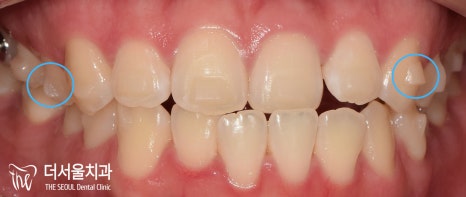

『인비절라인 기간 ’10개월’간의 기록 (초진)』

“저 입이 툭 튀어나와서 좀 집어넣고 싶어요.

근데 눈에 잘 띄는 철사들은 부담스럽더라고요.”

어?

아랫니가 윗니를 덮고 있는

‘반대교합(cross bite)’이 함께 나타나고 있군요.

정중선이 맞지 않는 것은 물론이며

전치부 치열에서 총생(crowding)도 함께 동반되었습니다.

이와 더불어,

전방으로 돌출되어 있는 모습이 관찰되네요.